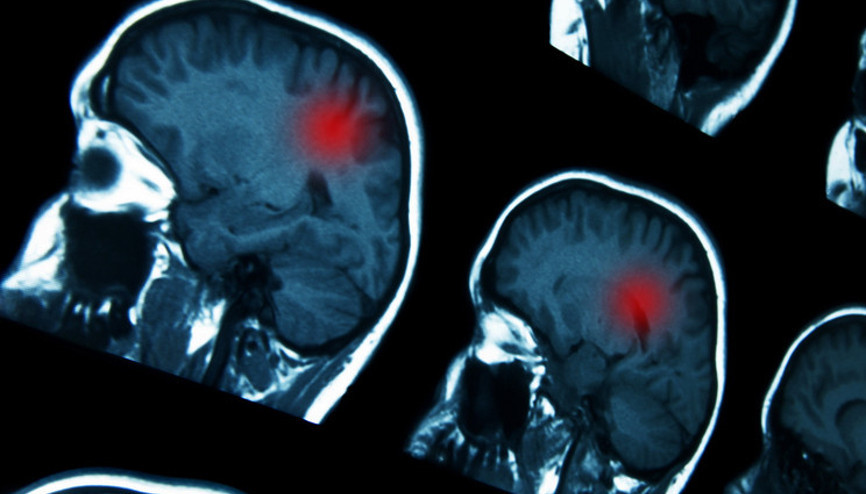

#Kelsey ParkerBazekol Hastanesi Beyin ve Sinir Cerrahisi Uzmanı Opr. Dr. Haluk Özer, bazen hiçbir bulgu vermeyen tümörler olmakla birlikte geçmeyen baş ağrısı, devam eden bulantı, sık ve sebepsiz kusmanın tümör olasılığını akla getirmesi gerektiğini belirterek, en ufak şüphede beyin MR’ı çekimi önerdi.